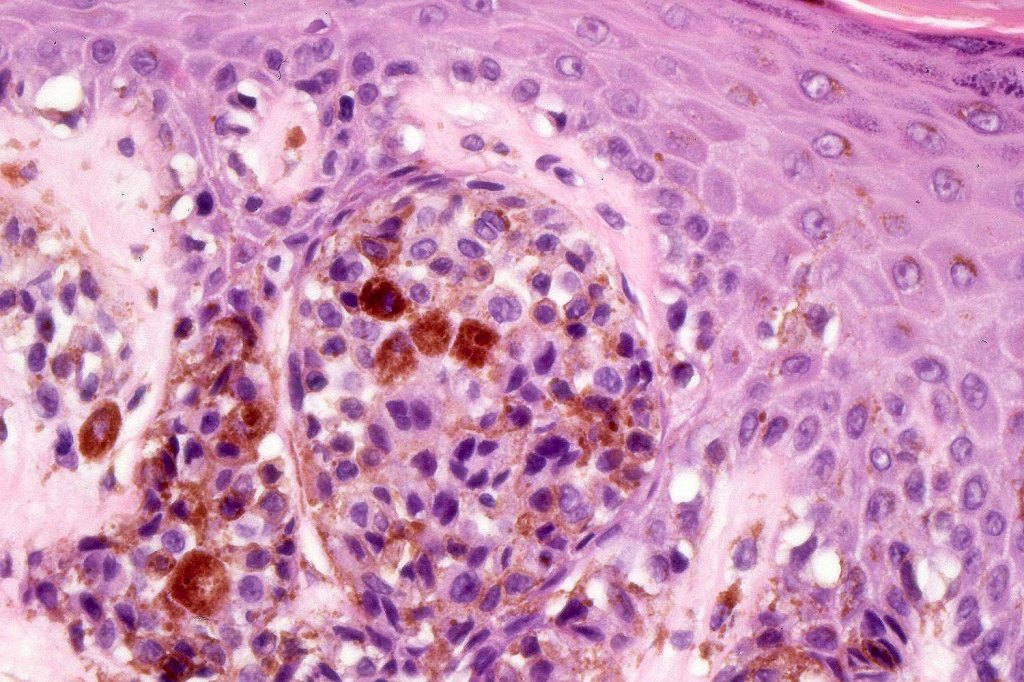

•Large dyscohesive nests with retraction artifact, not restricted to the tips of the epidermal ridges

•Heavy pigmentation (sometimes gray/green)

•Bridging common, often over multiple rete ridges

•Variable atypia (can be marked)

•Central pagetoid spread

•Superficial dermal atypia